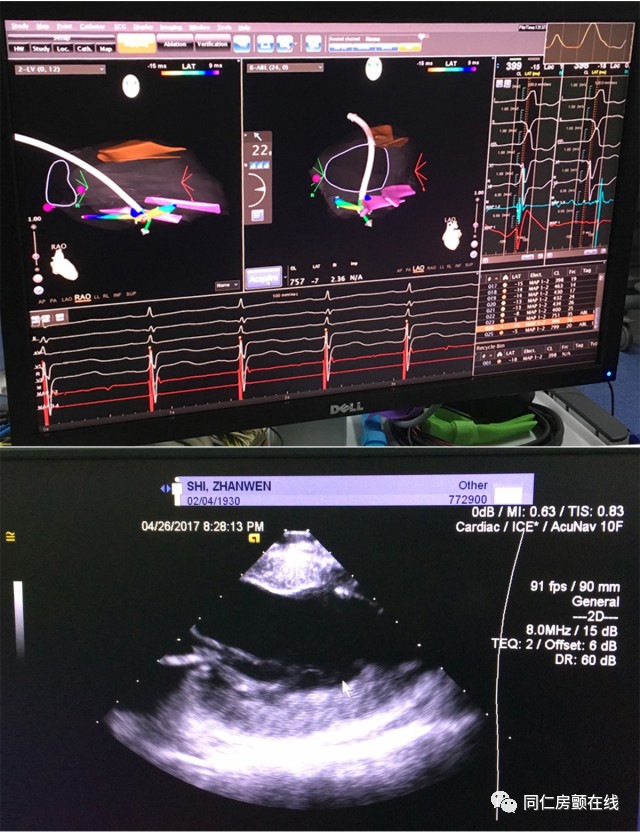

从患者心电图判断,我们怀疑这位患者的室性早搏起源于乳头肌。通俗的说,就是这种心律失常起源的部位结构复杂,消融难度相当大,手术成功率低。并且患者年龄大,还有严重的冠心病,消融治疗的风险很高。经过马长生主任、史旭波主任以及郭炜华教授的讨论,我们决定应用心腔内三维超声导管,在心腔内超声(ICE)技术的指导下为患者进行射频消融。正是得益于这项被叫做ICE的新技术,手术取得了极大的成功。

目前的射频消融,医生需要利用X线和三维标测系统,大致判断导管在心脏中的位置,而不能直接看到导管是否真正贴靠在目标结构上。心腔内超声技术(ICE)可以帮助介入医生更加直观地看到心脏里面的结构,还可以更加精确地定位消融导管的位置,为射频消融术提供了强大的指导作用。由于可以实时获知心腔内的情况,心腔内超声可以像透视一样实时指导消融的全过程,可以实时显示导管贴靠的情况,显著提高了手术的成功率;心腔内超声还能实时监测术中心腔内的变化,第一时间发现心包积液等并发症,提高了手术的安全性;此外,使用心腔内超声技术还可以有效减少X线的用量,减轻辐射对病人和医生的伤害。该项技术用于复杂性心房颤动(房颤)患者的消融治疗,不仅可以提高消融的有效性及安全性,而且还可为慢性肾功能不全、造影剂过敏的房颤患者带来福音。

CartoSound三维超声技术指导下的乳头肌起源室性早搏的射频消融

目前,心腔内三维超声技术在美国、欧洲和日本等国家的大型医学中心用于各类复杂心律失常的介入治疗。北京同仁医院心血管中心首次将CartoSound心腔内三维超声技术用于难治性室性早搏的治疗。这次手术标志着三维心腔内超声技术这把利剑真正进入了同仁心血管中心。今后,这项新技术将常规用于指导包括房颤在内的复杂难治性心律失常的介入治疗,将为导管消融治疗提供新的有力支持,为更多心律失常患者提供帮助!